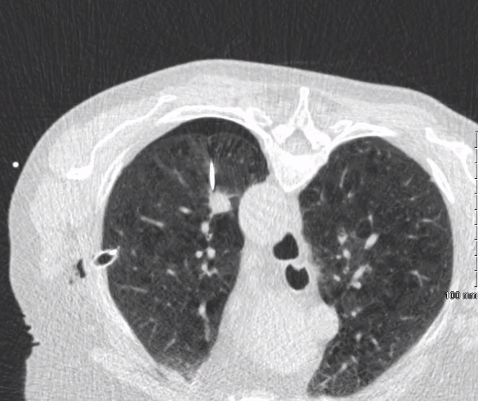

在严重肺气肿患者中预防性胸腔引流插入以促进重复CT引导肺活检 80岁高龄女性慢性阻塞性肺病晚期。左上肺叶针状病变,需活检,支气管镜无法检查。最初经皮CT引导肺活检导致气胸,胸腔引流插入和手术失败。值得注意的是,病人有气胸症状。

随诊影像显示病灶持续,PET/CT无明确结果。计划组织取样以确定治疗方法。由于目标位置和晚期肺气肿,重复气胸的可能性很大。重复经皮活检计划与预防性胸腔引流同时进行。